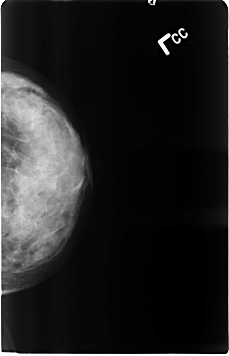

ics_version 1.0 filename B-3120-1 DATE_OF_STUDY 16 11 1994 PATIENT_AGE 50 FILM FILM_TYPE REGULAR DENSITY 4 DATE_DIGITIZED 25 2 1998 DIGITIZER LUMISYS LASER SEQUENCE LEFT_CC LINES 4624 PIXELS_PER_LINE 2976 BITS_PER_PIXEL 12 RESOLUTION 50 NON_OVERLAY LEFT_MLO LINES 4632 PIXELS_PER_LINE 2960 BITS_PER_PIXEL 12 RESOLUTION 50 NON_OVERLAY RIGHT_CC LINES 4616 PIXELS_PER_LINE 2960 BITS_PER_PIXEL 12 RESOLUTION 50 OVERLAY RIGHT_MLO LINES 4656 PIXELS_PER_LINE 2992 BITS_PER_PIXEL 12 RESOLUTION 50 OVERLAY |

FILE: B_3120_1.RIGHT_CC.OVERLAY TOTAL_ABNORMALITIES 1 ABNORMALITY 1 LESION_TYPE CALCIFICATION TYPE PUNCTATE-PLEOMORPHIC DISTRIBUTION N/A ASSESSMENT 4 SUBTLETY 3 PATHOLOGY BENIGN TOTAL_OUTLINES 1 BOUNDARY |